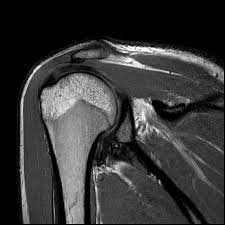

This is where the revolutionary technology of Musculoskeletal MRI entered her life, offering a beacon of hope. Musculoskeletal MRI is not just a medical procedure; it is a gateway to understanding the root cause of pain with precision. Unlike traditional diagnostic methods, it provides detailed images of bones, muscles, joints, and soft tissues, enabling doctors to pinpoint the exact problem area.

For Priya, this meant transitioning from a world of uncertainty to one where clarity and actionable solutions were within reach. Her orthopedist recommended a Musculoskeletal MRI to delve deeper into the underlying causes of her knee pain. The process was seamless, non-invasive, and surprisingly quick. The high-resolution images revealed a minor but significant tear in her meniscus, a diagnosis that had eluded previous X-rays and ultrasounds.